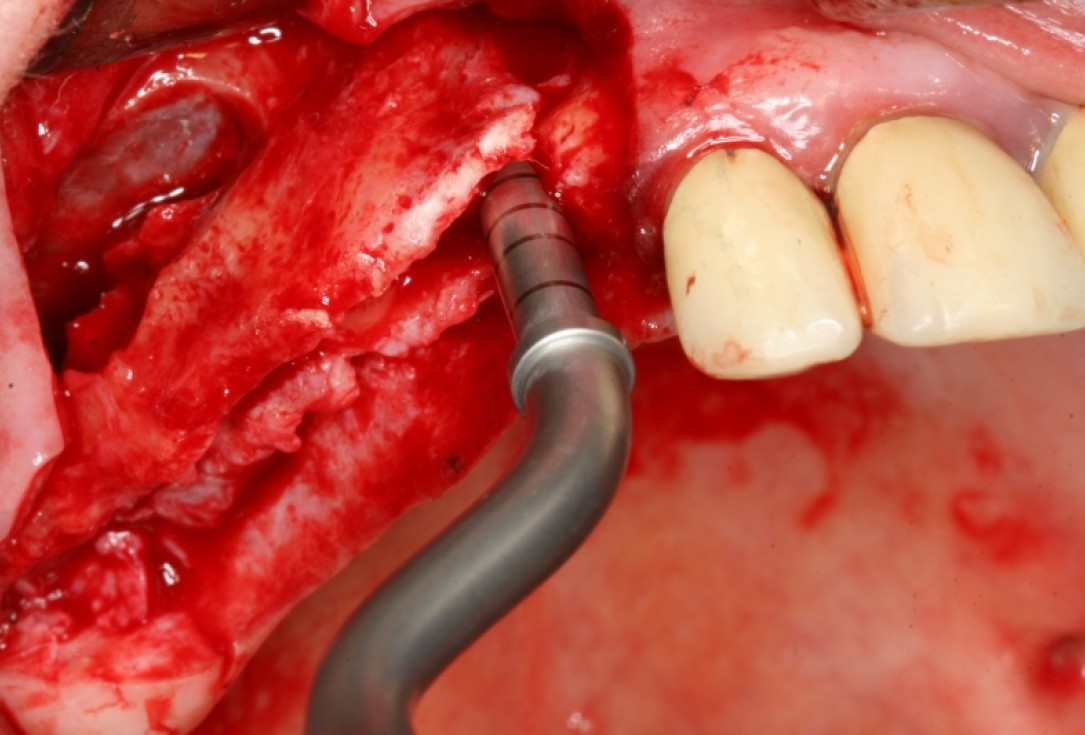

Implant insertion in atrophic alveolar ridge